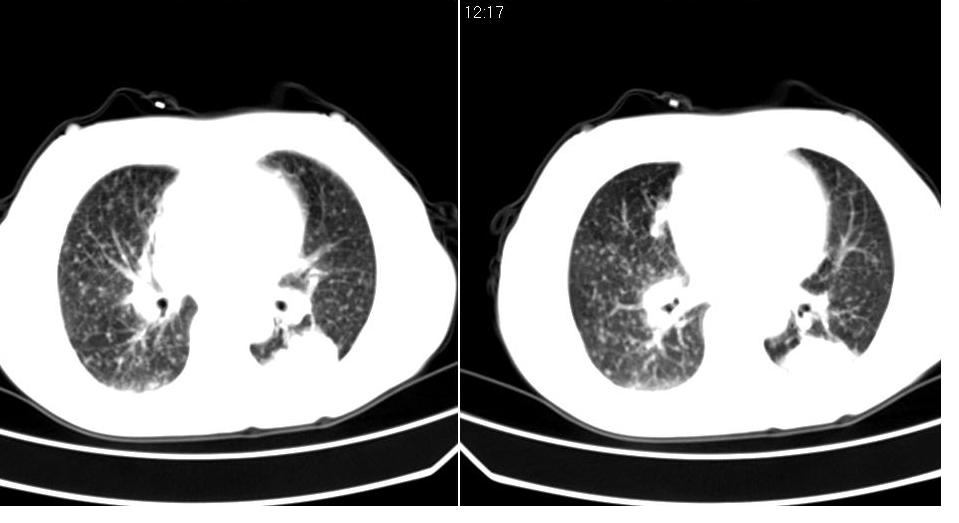

标题: CT16839:胸部CT平扫

女 50岁,在其他医院确诊肺癌.

支持 右肺上叶肺癌并两肺及纵隔转移。

考虑 肺癌伴肺及纵隔转移,心包膜增厚